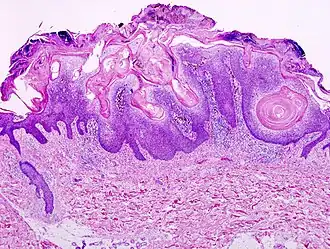

Ceratose seborreica

Ceratose seborreica é um crescimento não-canceroso benigno da pele que se origina a partir dos queratinócitos.